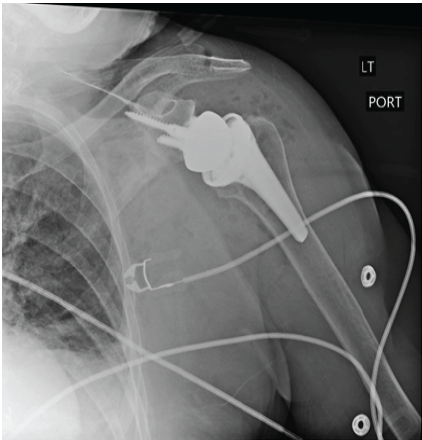

The patient discontinued warfarin 5 days before her scheduled arthroplasty procedure and began taking 60 mg enoxaparin twice daily. Enoxaparin was then held for 48 h before surgery. Given the patient’s history of APS and prior embolic episodes, timely reinitiation of anticoagulation with enoxaparin 24–48 h after the date of surgery was recommended by her Internal Medicine physician. As per the American Society of Hematology’s guidelines, if a patient’s INR is >1.5 on the date of surgery, it is recommended that procedures with a high bleeding risk do not proceed [15]. Our patient’s INR was 1.1 on the date of surgery. After general anesthesia was induced, the patient was placed in the beach chair position and a standard deltopectoral approach was performed. Access to the joint was obtained through a subscapularis tenotomy. A standard humeral neck osteotomy and soft tissue releases were performed. Implantation of the INHANCE™ reverse prosthesis (Johnson and Johnson MedTech, Raynham, MA, USA) was uneventful. The subscapularis tenotomy was repaired and the surgical wound was closed with absorbable suture. No significant bleeding was encountered. Drain placement was not needed. The patient was placed in a shoulder immobilizer with an abduction pillow and transported to the post-operative recovery room (Fig. 2). Total blood loss during the procedure was 150 mL and post-operative hemoglobin was 8.8 g/dL. Tranexamic acid 1 g infusion was administered at the beginning and end of the case for a total of 2 g.

Figure 2: Anterior-posterior radiograph of the left shoulder on the 1st post-operative day after reverse total shoulder arthroplasty, demonstrating a reduced shoulder with good alignment of the components.